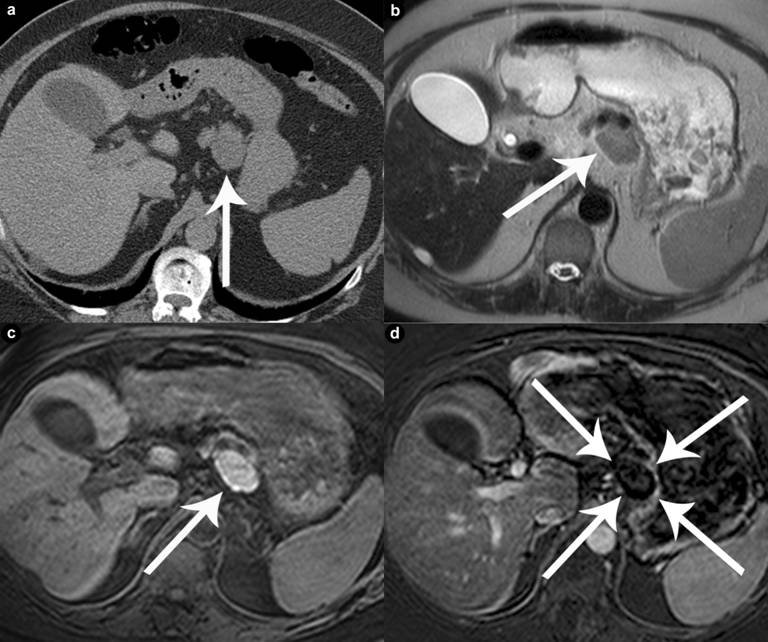

The final pathological reports in these six patients were consistent with lymphoepithelial cysts of the pancreas. The cysts were multiloculated and were lined with a well differentiated, keratinized squamous epithelium and associated with aggregates and sheets of benign lymphocytes (Figure 4). One of the cysts contained keratinaceous debris and one showed numerous small nodular projections, which protruded into the lumen.

Figure 4. Cyst wall lined by benign squamous epithelium with underlying lymphoid aggregates. Normal pancreas is present beneath this (Case #5). |